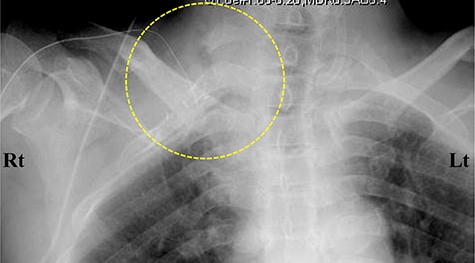

Contrast-enhanced computed tomography (CT) images of the thorax. (A) Axial view. (B) Coronal view. (C, D) Three-dimensional CT images. The subclavian artery (circle) was occluded due to a thrombus (arrow) at the level of the dysplasia of ribs.

The laboratory data revealed inflammation (white blood cell: 17 500/μl; C-reactive protein: 19.34 mg/dl). Although an increase in D-dimer levels (1.1 ng/ml) was not observed, the contrast-enhanced CT imaging revealed that the subclavian artery was occluded, and a successive distal arterial embolism was produced (Fig. 4). We diagnosed him with an acute arterial occlusion associated with TOS.